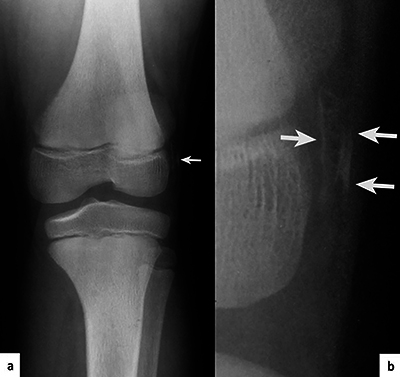

Teaching point: Some genetic syndromes have characteristic features that allow for their diagnosis to be made based on radiological findings.